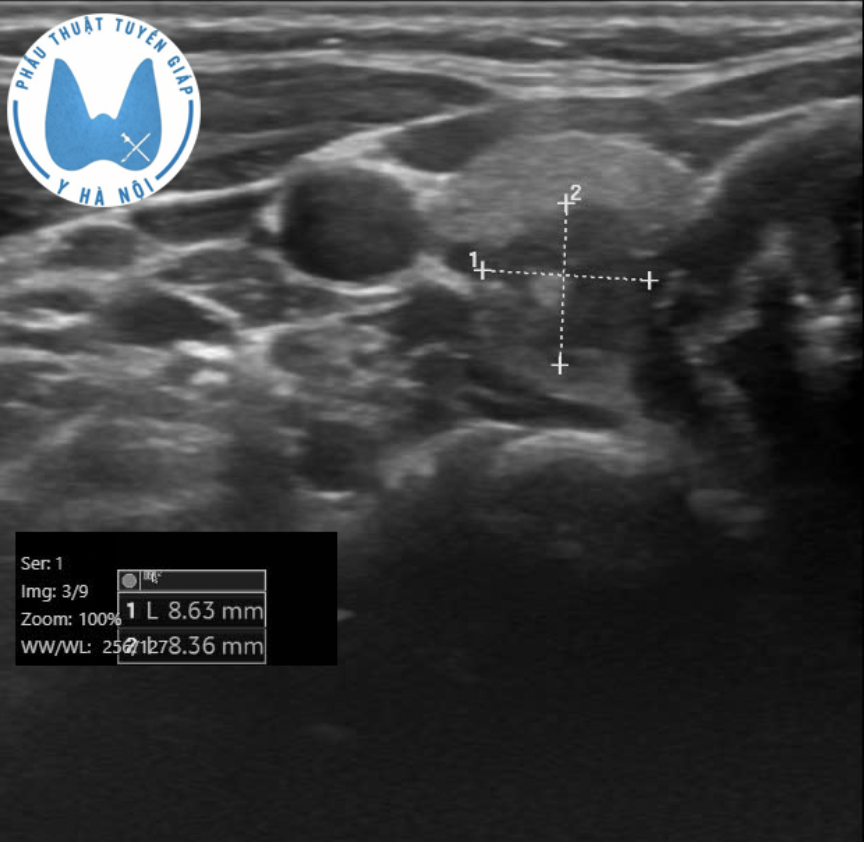

Một khối u chỉ 8 × 8 mm. Với nhiều người, đó có thể chỉ là một phát hiện “tình cờ”, thậm chí có ý kiến cho rằng chưa cần can thiệp gì ngay.

Gần đây chúng tôi phẫu thuật cho một bệnh nhân nữ trẻ tuổi. Em đi khám sức khỏe và vô tình phát hiện một nhân tuyến giáp kích thước 8 × 8 mm. Đáng nói, trước đó, em đã được siêu âm tại hai bệnh viện chuyên khoa, và kết quả đều không ghi nhận hạch cổ bất thường.

Kết quả lần siêu âm này chỉ phát hiện duy nhất một hạch có đặc điểm nghi ngờ di căn. Các hạch còn lại trên hình ảnh đều mang đặc điểm của hạch lành tính.